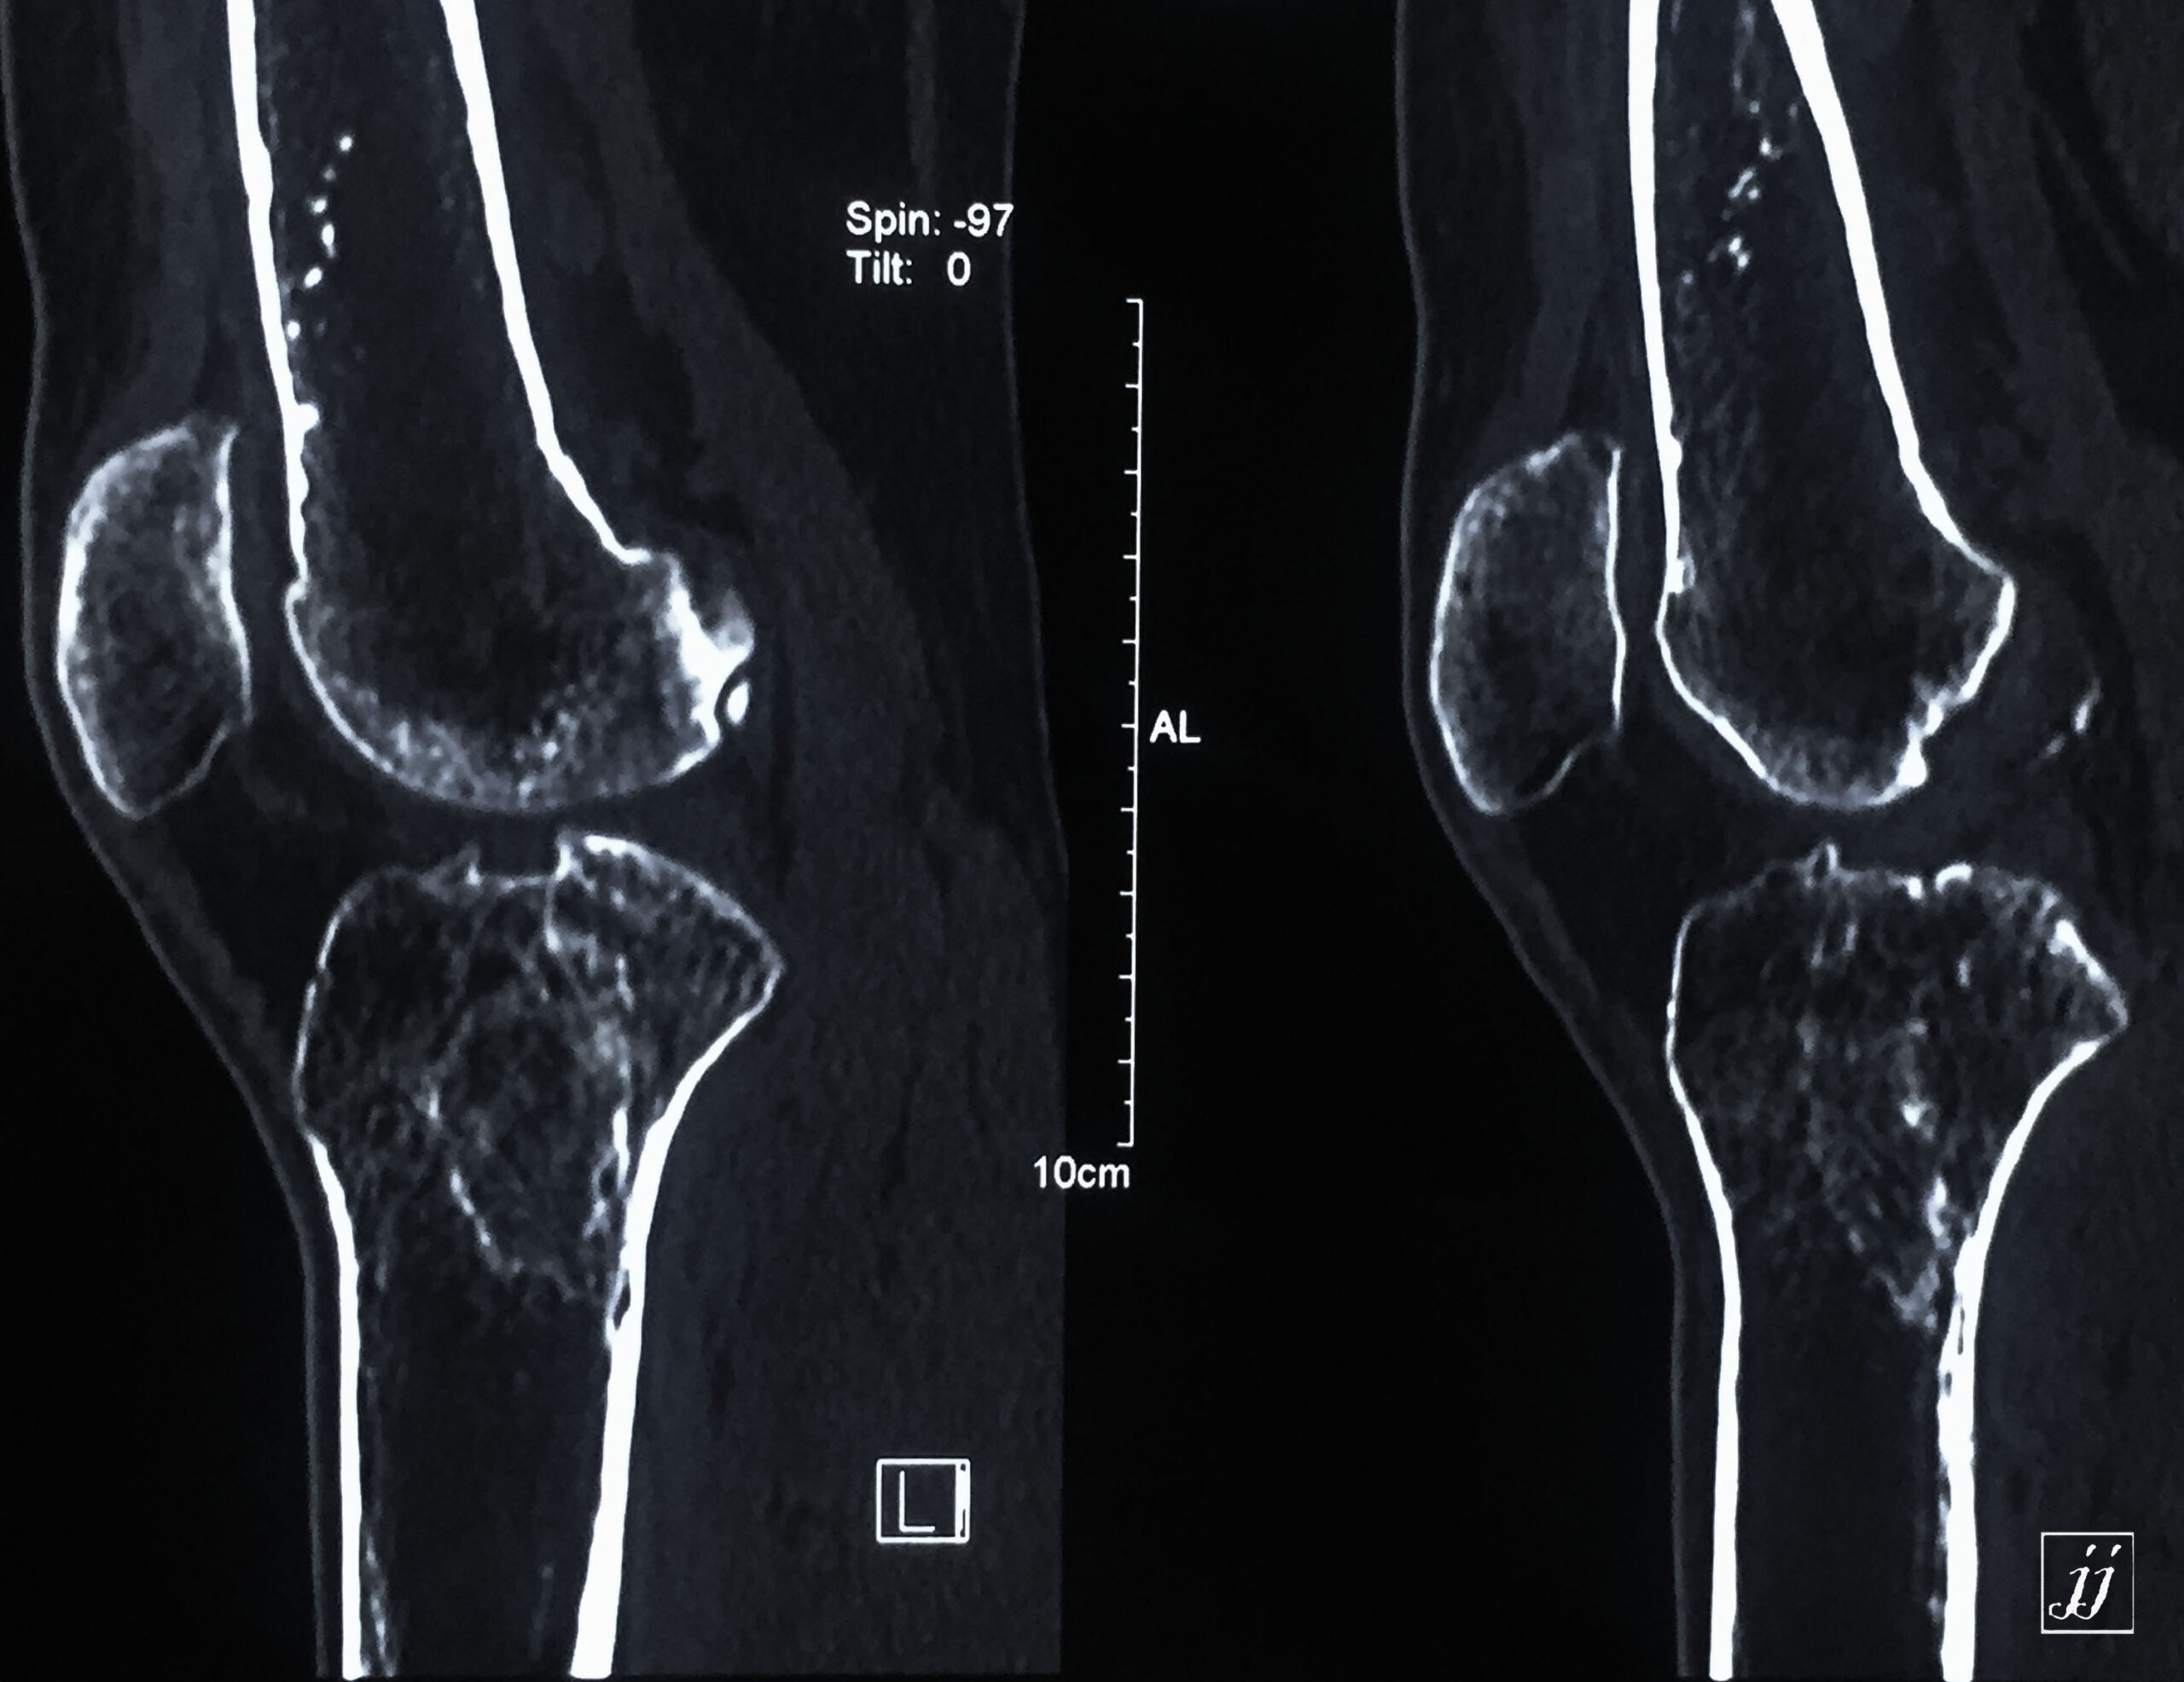

MSK- proximal tibia fracture and infection (22)